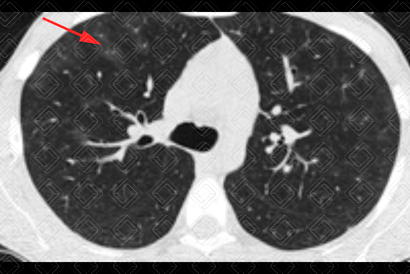

Texto alternativo para a imagem Créditos: Dra. Elazir Mota - Rio de Janeiro/RJ

Descrição das imagens: Tomografia computadorizada do tórax evidenciando tênues lesões em vidro fosco (setas vermelhas) dispersas pelo parênquima pulmonar, por hemorragia alveolar. Caso confirmado de leptospirose com apresentação pulmonar.

• Tomografia computadorizada de tórax: Opacidades em vidro fosco, pavimentação em mosaico (padrão caracterizado por áreas em vidro fosco associado a espessamento dos septos interlobulares) e consolidações são os achados mais frequentemente observados e traduzem a presença de hemorragia alveolar (uma complicação que ocorre na leptospirose), como demonstrado nas imagens acima. Sua distribuição é preferencialmente periférica, subpleural e nas regiões póstero-inferiores dos pulmões. Cabe lembrar, no entanto, que são achados de imagem inespecíficos, assim como na radiografia. O diagnóstico só pode ser sugerido diante de uma boa história clínica.